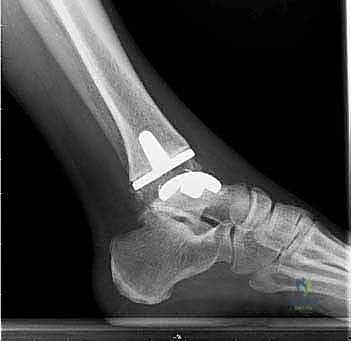

4. تركيب المفصل الصناعي (Implantation)

يتكون مفصل الكاحل الصناعي الحديث عادة من ثلاثة أجزاء:

* قطعة معدنية علوية: تُثبت في عظمة الظنبوب (الساق).

* قطعة معدنية سفلية: تُثبت في عظمة الكاحل.

* قطعة بلاستيكية (بولي إيثيلين عالي الكثافة): توضع بين القطعتين المعدنيتين لتنزلق بسلاسة وتمتص الصدمات، محاكيةً وظيفة الغضروف الطبيعي.

يتم تثبيت هذه الأجزاء بإحكام (إما عن طريق الضغط المباشر لتشجيع نمو العظم حولها، أو باستخدام أسمنت طبي خاص).